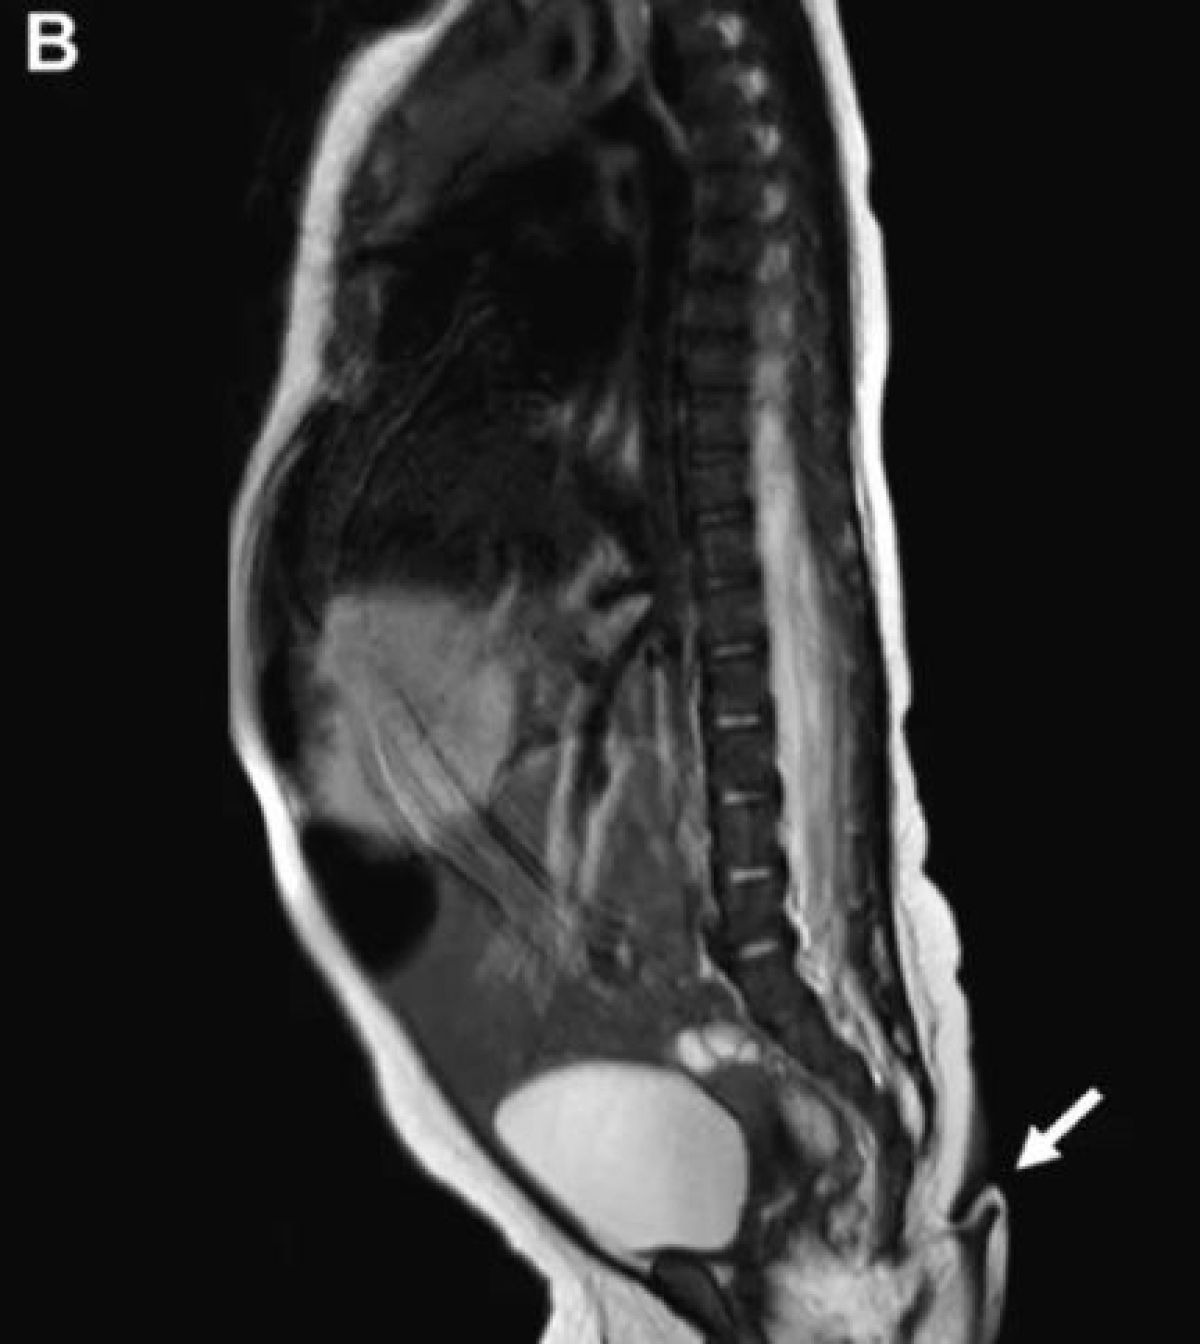

Ko je deklica v mehiški porodnišnici Ciudad de Mexico prijokala na svet, so zdravniki pri pregledu prešteli čisto vse: roki, nogi, nos, ušesa in še en dodatek, repek. Zdravniki so bili začudeni in so izmerili repek, meril je dobrih 6 centimetrov. Njena pritiklina spada v kategorijo pravih človeških repov, saj je pokrit s kožo.

Po dveh mesecih po rojstvu so izvedli operacijo in deklico brez kakršnih koli zapletov osvobodili točno 5,7 centimetrov dolge in 5 milimetrov široke tvorbe. Malo bolnico so z bolnice odpustili povsem zdravo.